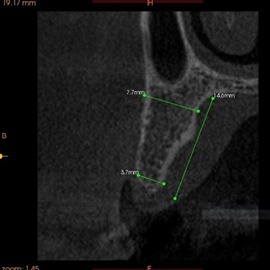

Pacjentka lat 72, od kilkudziesięciu lat chorująca na cukrzyce I typu, obecnie od 10 lat na pompie insulinowej. Profesor medycyny, siostrzenica pacjentki prowadzi swoją ciocię diabetologicznie, pacjentka świadoma zagrożeń przy zabiegach regeneracji kości i implantacji w takim ogólnym stanie zdrowia. Po rekonstrukcji tkanek miękkich i kości osadzono dwa implanty o średnicy 5,0 mm. Na zdjęciu śródzabiegowym widać zadowalające wyniki rekonstrukcji tkanki kostnej. Po upływie kilku miesięcy wykonano nadbudowę protetyczną.